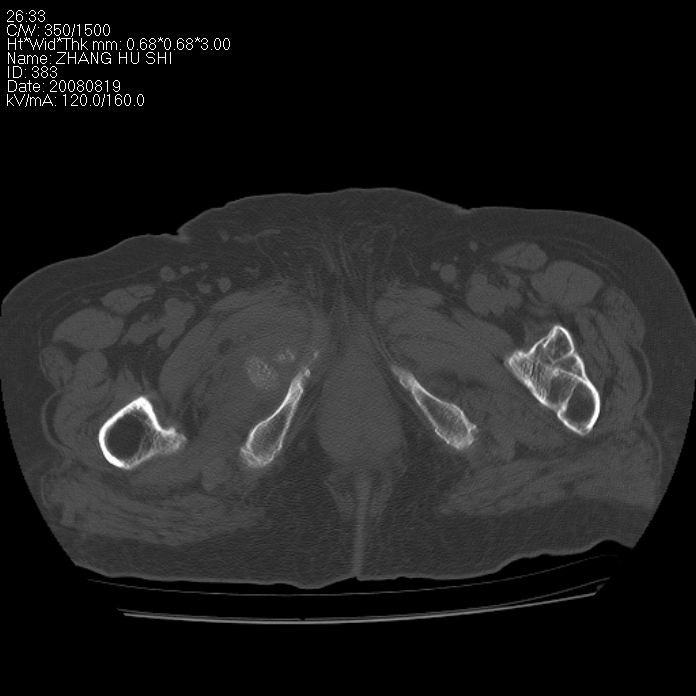

标题: CT15287:女 93岁 右髋关节疼痛 原左侧粗隆间骨折 CT发现右耻 [打印本页]

标题: CT15287:女 93岁 右髋关节疼痛 原左侧粗隆间骨折 CT发现右耻

支持转移并周围软组织侵犯右闭孔内肌侵犯,但tb不能完全除外。

耻骨软骨肉瘤可能性大